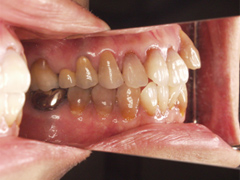

写真(1)口内写真

正確な診断

院長の吉本の診断は、以下の2つでした。

・虫歯の進行により、歯の根っこに膿が出来てしまった

・咬み合わせが悪いことにより、虫歯になりやすい(バイ菌がたまりやすい)